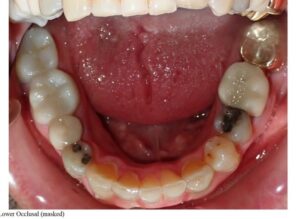

Case 2 – Attachments on U/L 2s

| Initial | 5-month progress, 14 aligners |

![]() | ![]() |